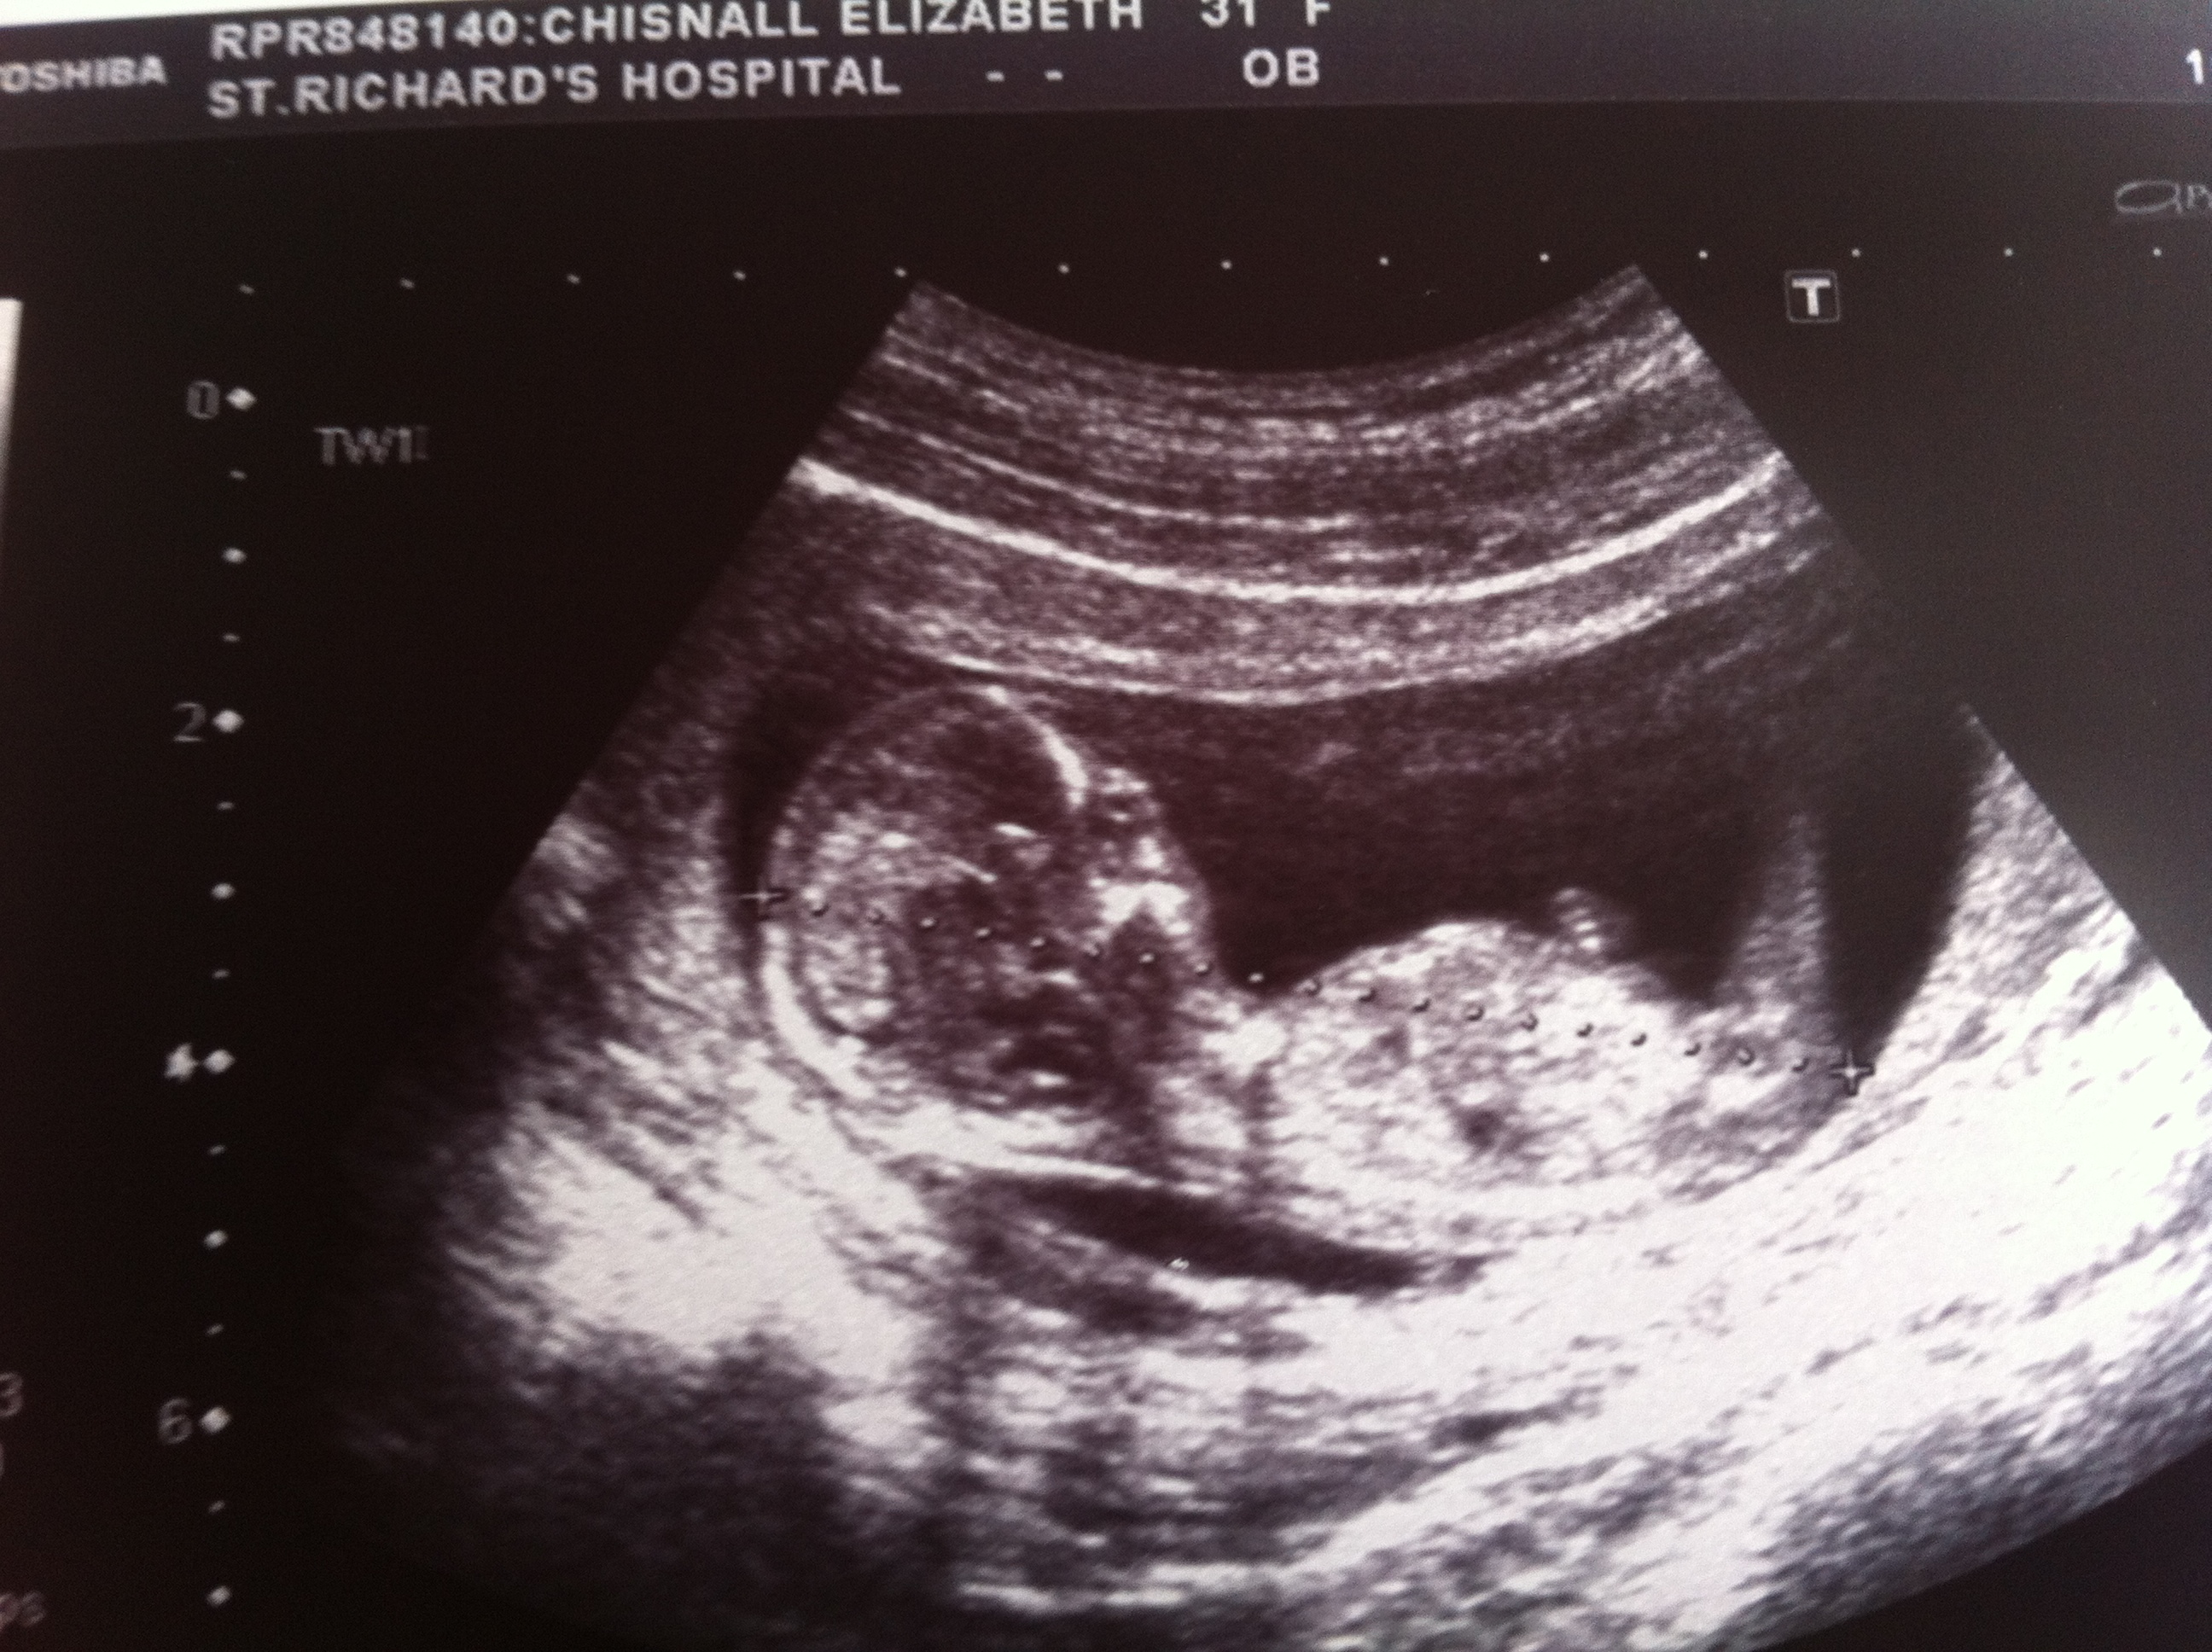

hey so super shock 2 passengers!

don't think any of these are great nub shots but look at them together so cute!

Update sadly twin two only made it to 15 weeks

Update confirmed dd at 17 wks plus unknown angel baby ;-(